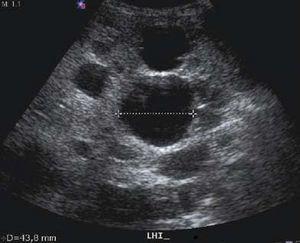

Figura 1. USG hígado: lóbulo hepático izquierdo.